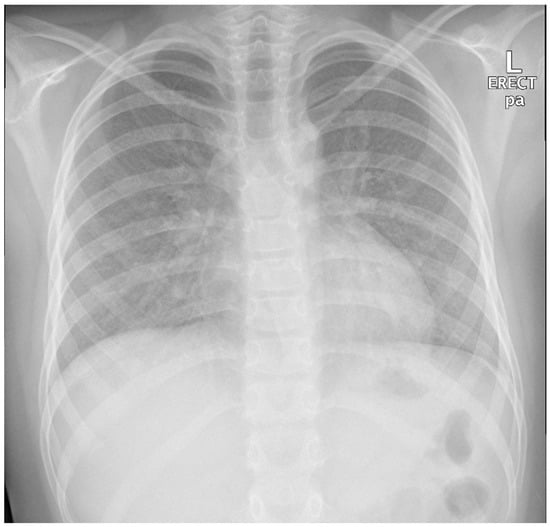

An 11-year-old, previously healthy boy presented to the emergency department with a 1-week history of dry cough, shortness of breath, and low-grade fever, with no associated symptoms of expectoration, hemoptysis, wheezing, contact with sick people, or recent travel, and no history of weight loss. His past medical history was unremarkable, and he was fully vaccinated in accordance with his age. Physical examination revealed an afebrile child with remarkable tachypnea with moderate respiratory distress, desaturation requiring oxygen, subcostal and intercostal retractions, and decreased air entry bilaterally on lung auscultation without wheeze or crackles. A chest X-ray (CXR) showed bilateral diffuse miliary nodules (Figure 1). The child required pediatric intensive care unit (PICU) admission for close observation and further management. He was started on IV cefuroxime and oral clarithromycin and Tamiflu as treatment of viral pneumonitis with possible secondary bacterial infection and required a high-flow nasal cannula (HFNC) for oxygen support. Respiratory virus polymerase chain reaction (PCR) showed bocavirus positive, at which point Tamiflu was discontinued. The child remained tachypneic with persistent respiratory distress and continued to require high oxygen therapy. Repetition of his CXR imaging showed persistent diffuse bilateral miliary infiltrations. A CT scan of the chest showed diffusely reticular-nodular opacities in both lungs involving lung bases and the posterior segments of the right and left upper and lower lobes with irregular bronchovascular marking (Figure 2). Purified protein derivative (PPD) and QuantiFERON-Gold showed negative results. The child showed improvement of his symptoms on day 10 of his hospital admission and was able to be weaned off oxygen support, and he was discharged in a stable general condition with a mild dry cough.

Figure 1.

Patient first chest X-ray (CXR) showed bilateral diffuse miliary nodules.